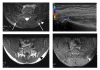

Background: The presence of enthesitis (insertional inflammation) in patients with juvenile idiopathic arthritis (JIA) is difficult to establish clinically and may influence classification and treatment of the disease. We used ultrasonography (US) and color Doppler (CD) imaging to detect enthesitis at the small and deep-seated proximal insertion of the gluteus medius fascia on the posterior iliac crest where clinical diagnosis is difficult. The findings in JIA patients were compared with those obtained in healthy controls and with the patients' MRI results.

Methods: Seventy-six proximal gluteus medius insertions were studied clinically (tenderness to palpation of the posterior iliac crest) and by US and CD (echogenicity, thickness, hyperemia) in 38 patients with JIA and in 38 healthy controls, respectively (median age 13 years, range 7-18 years). In addition, an additional MRI examination of the sacroiliac joints and iliac crests was performed in all patients.

Results: In patients with focal, palpable tenderness, US detected decreased echogenicity of the entheses in 53% of the iliac crests (bilateral in 37% and unilateral in 32%). US also revealed significantly thicker entheses in JIA patients compared to healthy controls (p < 0.003 left side, p < 0.001 right side). There was no significant difference in thickness between the left and right sides in individual subjects. Hyperemia was detected by CD in 37% (28/76) of the iliac crests and by contrast-enhanced MRI in 12% (6/50).

Conclusions: According to US, the gluteus medius insertion was thicker in JIA patients than in controls, and it was hypoechoic (enthesitis) in about half of the patients. These findings may represent chronic, inactive disease in some of the patients, because there was only limited Doppler flow and MRI contrast enhancement. The present study indicates that US can be useful as an adjunct to clinical examination for improved assessment of enthesitis in JIA. This may influence disease classification, ambition to treat, and choice of treatment regimen.